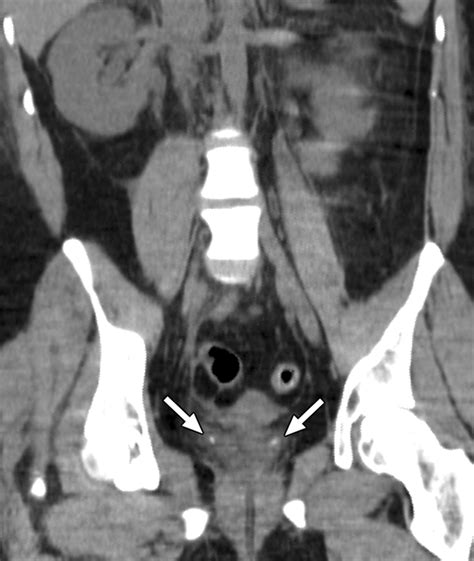

• Non-contrast CT Scan: The gold standard for identifying stones, their size, and their exact location.

• ureterovesical junction stone ct